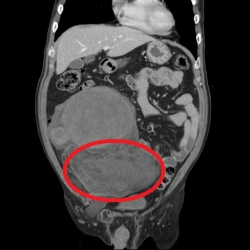

脂肪會癌變?6旬翁腹股溝長「30公分」超大腫瘤 - 健康醫療網 - 健康養生新聞資訊網路媒體

2022-05-28 18:00:00 by 健康醫療網 @ 健康醫療網 [引用來源]

68歲劉先生近日因腹部疼痛就醫,經電腦斷層檢查發現,在腹股溝處有一個近30公分大的腫瘤,大千綜合醫院泌尿科醫師李承哲安排手術切除後進行病理切片,報告證實為惡性脂肪肉瘤,所幸腫瘤並未轉移。劉先生術後恢復良好,目前持續追蹤避免復發。 李承哲表示,脂肪肉瘤常發生於四肢及後腹腔內,是深層軟組織異常且具有侵犯性的惡性腫瘤,為罕見的癌症疾病。出現在四肢的脂肪肉瘤多是腫大的硬塊,會有疼...... [閱讀更多]